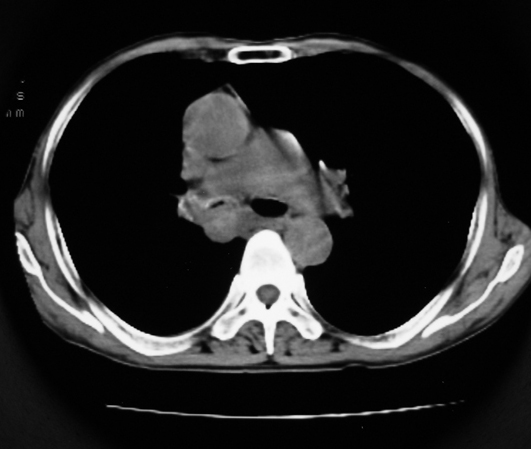

以下是引用同在2007-1-27 14:13:00的发言:[br]支持右侧中央型肺癌伴阻塞性病变.

以下是引用zjzjr在2007-1-27 16:56:00的发言:[br]支持右肺中心型肺癌伴阻塞性肺炎.